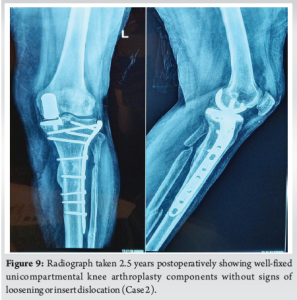

By 6 months, she had regained full range of motion (130°), could sit cross-legged, and walked independently without aids (Fig. 7 and 8). At 2 years and 8 months from the primary UKA (2 years and 5 months post-fracture fixation), the UKA components remained well-fixed, and her OKS was 46 (Fig. 9).